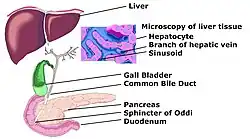

Hepatology is the branch of medicine that incorporates the study of liver, gallbladder, biliary tree, and pancreas as well as management of their disorders. Although traditionally considered a sub-specialty of gastroenterology, rapid expansion has led in some countries to doctors specializing solely on this area, who are called hepatologists.